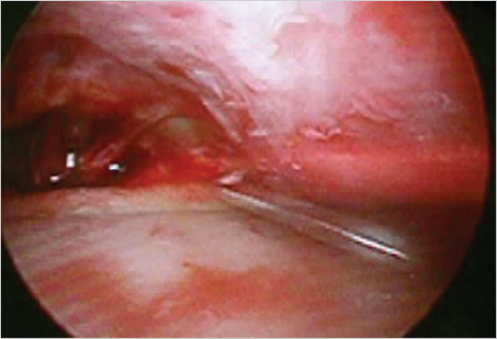

The marked skin and subcutaneous tissue are excised above the musculo-aponeurotic tissue. The galea and the periosteum are bluntly separated with a closed hemostat dissecting along the muscle fibers to avoid damage of the local sensory nerves. Using a curved periosteal elevator, the subperiosteal dissection extends to the supraorbital rims and to the frontotemporal line (Fig. 21‑3). Dissection is extended to the nasal tip to release the procerus. Direct visualization is obtained using a lighted rigid endoscope (Fig. 21‑4) and endoscopic video monitor (Fig. 21‑5). An optical cavity is created using a sheath around the scope to elevate the soft tissue off the lens. In addition, three nylon suspension sutures are placed externally just above the brow line (Fig. 21‑6). Divergent traction is placed on the sutures. The traction on the sutures helps create an optical cavity.

The supraorbital periosteum is divided completely to the level of the lateral orbital rims with an endoscopic carpal tunnel hook knife scalpel. Resection of the corrugators, procerus, and other depressors is achieved bluntly with a grasping forceps. The supratrochlear and supraorbital nerves are identified and preserved. The glabellar region is inspected after resection to ensure that the contour is smooth and not depressed or irregular. If there is any depression, a small amount of fat or SMAS can be used to fill the area (Fig. 21‑7, Fig. 21‑8, Fig. 21‑9).